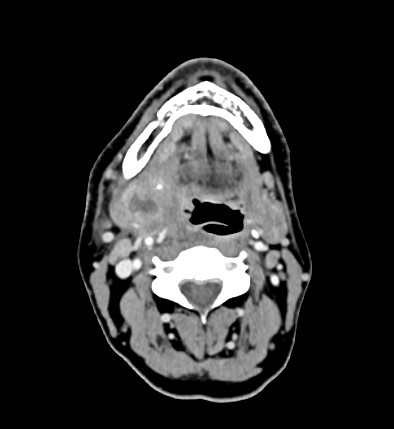

Un homme de 45 ans, consulte aux urgences pour une tuméfaction mandibulaire droite évoluant depuis dix jours, associée à une odynophagie et une limitation progressive de l'ouverture buccale. Malgré un traitement par anti-inflammatoires prescrit initialement pour une suspicion de kyste, l'état du patient se péjore avec apparition d'une aphagie aux solides.  L'examen clinique révèle une tuméfaction sous-mandibulaire droite de 5 cm, douloureuse et mobile, avec une ouverture buccale limitée à 2-3 cm. Le bilan biologique montre un syndrome inflammatoire avec hyperleucocytose à 12,6 G/l et CRP à 116 mg/l.

Le CT-scanner cervical (cf. image) confirme une sialadénite abcédée de la glande sous-mandibulaire droite secondaire à un sialolithe proximal du canal de Wharton, sans complication vasculaire.

Image proposée par Hôpital de La Tour.